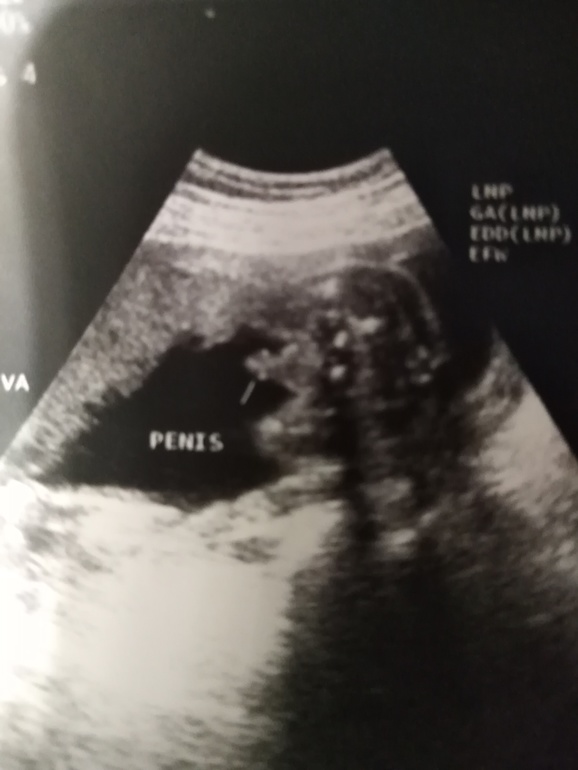

Вот наш пенис в 22н5д))))